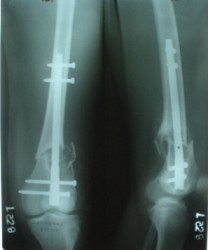

1

2

I attached an example of C2 fracture with result of the same technique in 5 months.